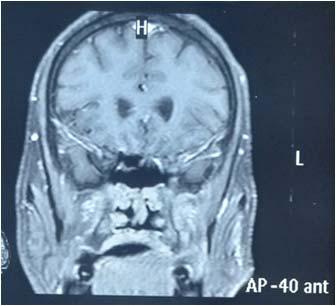

We found a strong positive correlation between abnormal EEG and abnormal Neuroimaging with Correlation coefficient of 0.902, (P- Value 0.0138) but almost no correlation found between normal EEG with normal Neuroimaging (Figs 1-4).

About 23% of patients with adult onset first seizure has metabolic derangement and the most common etiology was Dyselectrolytemia. The most common Central Nervous System (CNS) Infection as detected by CSF study was viral meningoencephalitis followed by Tuberculous Meningitis. The most common CNS lesion detected by CT studies as well as by MRI Brain was infarction and ring lesion, the two Neuroimaging studies corroborated in 75.38% of Seizure patients. Abnormal discharge in EEG found in34% cases. In majority patients EEG report was normal. EEG abnormality was more common in patients with Focal Seizure rather than GTCS patients. Thus, the most common etiology of first Seizure onset at adult age over 18 years were metabolic derangements (16.92%), CNS Infection or Inflammation (15.38%) and intracerebral Space occupying lesion (15.38%), usually ring lesion, tumors and Metastasis. Idiopathic Seizure found in 7.69% patients. The Correlation between abnormal Neuroimaging and abnormal EEG is strongly positive and statistically significant (P -Value = 0.013) but the same is not true in cases of normal Neuroimaging and normal EEG findings.